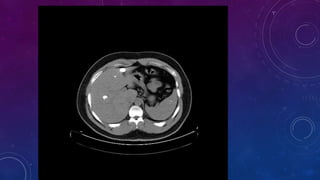

• Large rim calcified cyst in the spleen, likely

benign. This could be secondary to previous

trauma.